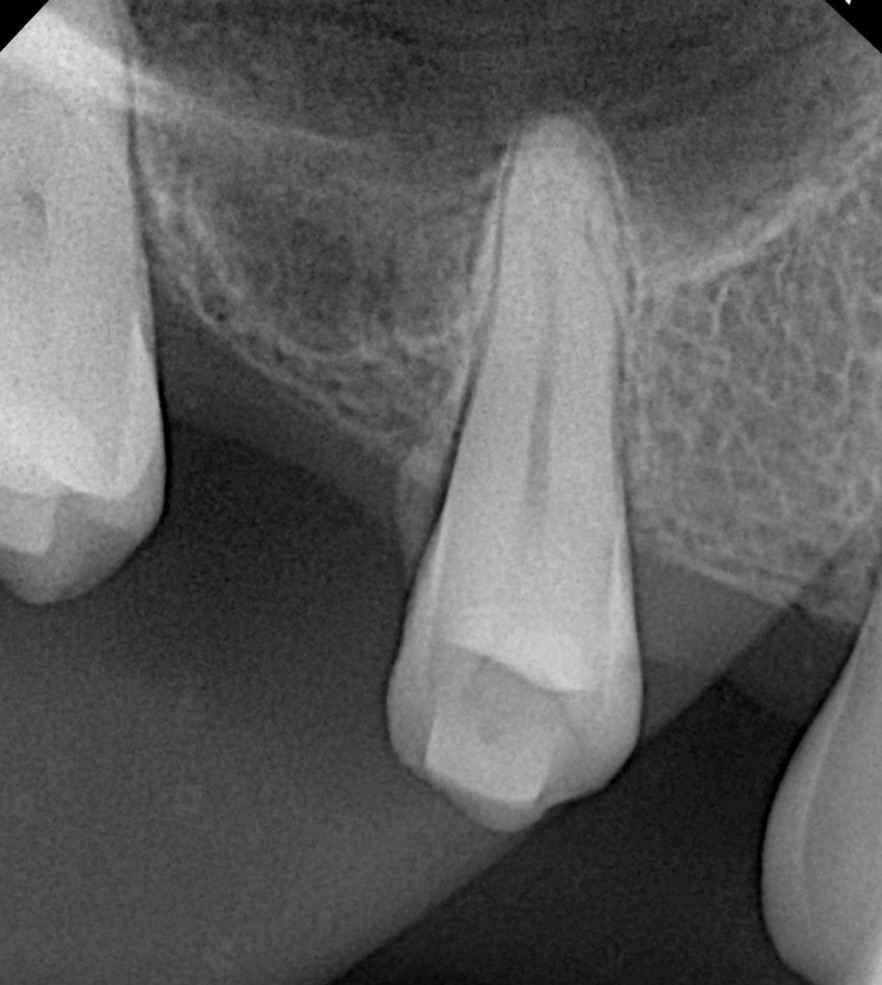

After verifying intact sinus membrane integrity via the Valsalva maneuver, particulate bone graft (allograft + synthetic blend) was incrementally packed into the osteotomy using osteotomes (Fig 3). Approximately 2 mm of membrane elevation was achieved beyond the sinus floor without perforation.